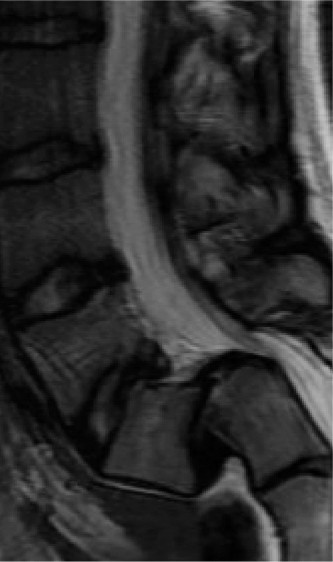

Figure 1–3

The correct answer is (B). The clinical scenario describes a patient with central cord syndrome (CCS). CCS continues to be the most common incomplete spinal cord injury accounting for 15.7% to 25% of all spinal cord injuries. The characteristic presentation is an extension moment injury in a previously spondylotic and stenotic spine. Figures 1–1 to 1–3 demonstrate a spondylotic spine with central narrowing and CSF effacement that is worst at the C3–4 level. Bleeding, edema, and/or Wallerian degeneration lead to damage of the lateral corticospinal tract which is the main descending motor tract in the spinal cord. The more central anatomic position of the homunculus to the upper extremities places them at greater risk than those to the lower extremities. As such, injury to the lateral corticospinal tract is characterized by upper more than lower extremity involvement and motor deficits being more pronounced than sensory deficits.